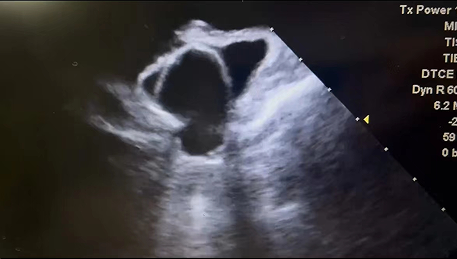

此例手术由韩稳琦博士和酉鹏华博士通过ICE指导下进行,通过ICE精准构建心脏模型、直视下穿刺房间隔,结合三维标测系统,精准、高效地完成双侧肺静脉隔离。后通过ICE及左心耳造影评估左心耳特征为下缘短,上缘折角大的短颈鸡翅型心耳,利用12F导引系统鞘管和猪尾导管在DSA肝位下同时造影,测量左心耳开口25.12mm,最大可用锚定区深度19.71mm,最终选择31mm规格watchman FLX封堵器的植入。ICE从不同角度检查即将释放的WATCHMAN FLX左心耳封堵器,观察封堵器位置、露肩、残余分流和压缩比情况,明确封堵器位置合理,无明显露肩,完全封堵无残余分流,封堵器位置良好。随后在ICE下观察及DSA透视下作牵拉试验,直到最后一次牵拉与前一次牵拉比较无位置改变,压缩比无明显变化,符合封堵器释放的“PASS”原则后完全释放封堵器。

图1 ICE观察测量左心耳开口及深度

图3 术后ICE观察测量Watchman FLX封堵器位置